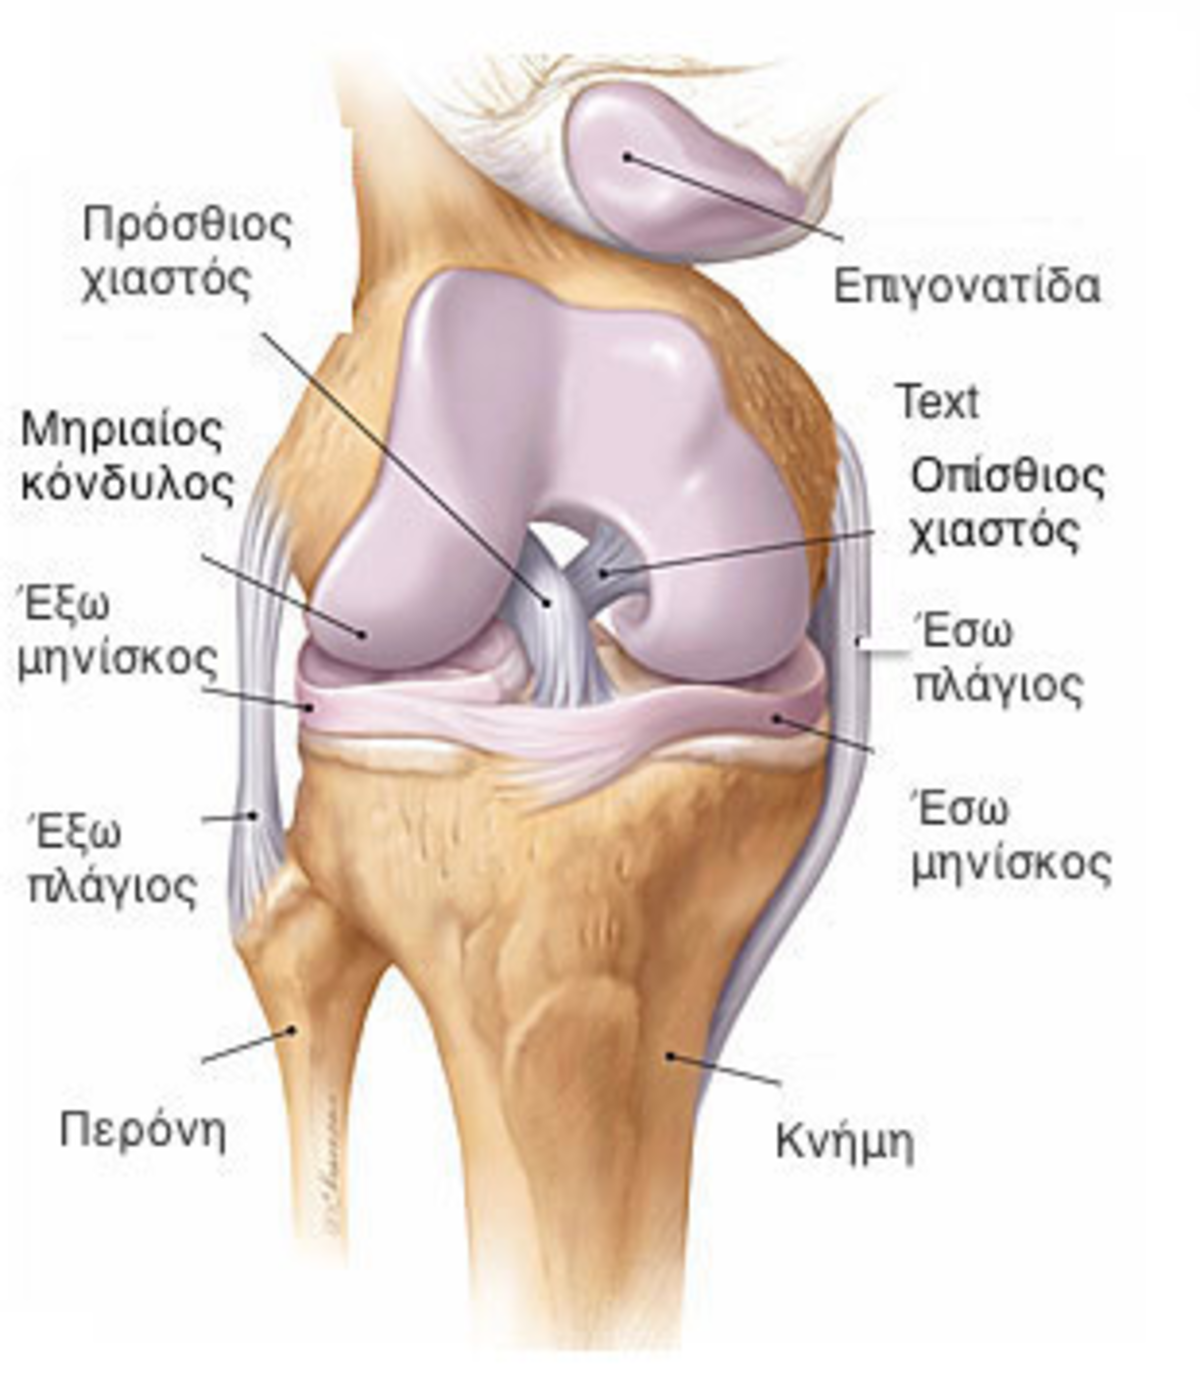

- Εξάρθρωση επιγονατίδας. Αυτό συμβαίνει όταν το τριγωνικό οστό (επιγονατίδα) που καλύπτει το μπροστινό μέρος του γονάτου σας βγαίνει εκτός θέσης και “γλιστρά” συνήθως προς το εξωτερικό του γονάτου σας. Σε ορισμένες περιπτώσεις, η επιγονατίδα μπορεί να παραμείνει εκτοπισμένη και θα είστε σε θέση να δείτε την εξάρθρωση εξωτερικά.